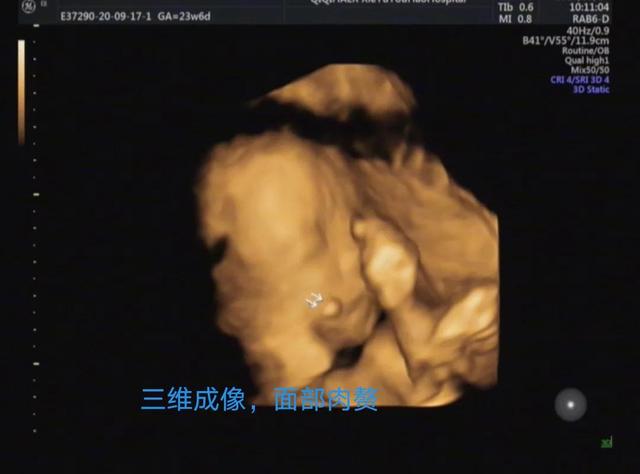

妈妈们更关心的是2D超声和3D超声的区别,简单的科普讲解,超声医生通过多切面和动态2D超声诊断畸形,3D成像只是在必要的时候起到辅助作用。胎儿表面结构的三维图像客观真实。一旦出现胎儿体表畸形,如唇裂、脑膨出、脊柱裂、脐膨出、腹裂、四肢、手脚畸形等,三维影像可以让孕妇及其家属一目了然,便于产科医生或儿科医生根据实际情况提供建议和意见,方便选择下一步的治疗方案。这里有几个小案例,读者可以自己体验一下。

案例1

比如病例1和病例5,外科医生和母亲可以直观地看到异常,医生可以相对容易地解释。妈妈和家人可以参考直观的3D成像,更透彻的了解,更安心。